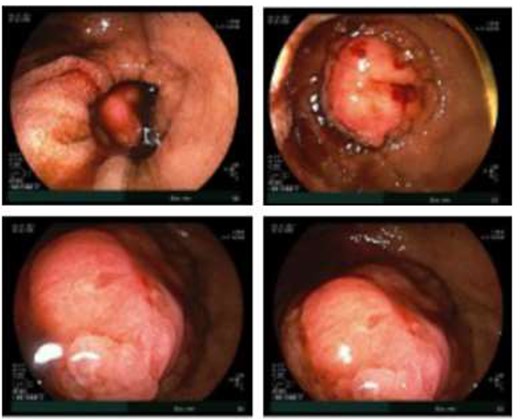

Double balloon enteroscopy revealing a 3 cm mass located in the distal jejunum/proximal ileum.

Given the patient’s anemia, melena and small bowel thickening, the patient was referred for upper and lower endoscopies, neither of which revealed the etiology of the patient’s symptoms. A pill endoscopy was also performed to evaluate the small intestine, though this was also unremarkable. The patient therefore underwent a double balloon enteroscopy, which was significant for a 3 cm small bowel mass located in the distal jejunum/proximal ileum (Fig. 2). The mass was biopsied and concerning for an adenocarcinoma. As a subsequent staging workup was negative for distant metastasis, the patient was taken for an exploratory laparotomy and small bowel resection. At the time of surgery, it was noted that the small bowel mass was located within an undiagnosed Meckel’s diverticulum (Fig. 3). The resected specimen was sent to pathology, which was significant for a moderately to poorly differentiated adenocarcinoma arising from a small bowel diverticulum, which was invading through the muscularis propria and into subserosal soft tissue with lymphovascular invasion (Fig. 4). The patient was therefore diagnosed with a Stage IIB (T4, N0) small bowel adenocarcinoma. After resection, the patient’s post-operative course was unremarkable, and he was discharged home on post-operative day 3. He was referred to medical oncology and is now receiving adjuvant capecitabine with oxaliplatin. As the patient’s resected specimen displayed negative margins, after completing the standard of care chemotherapy protocol, he will undergo active surveillance in accordance with the National Comprehensive Cancer Network guidelines.